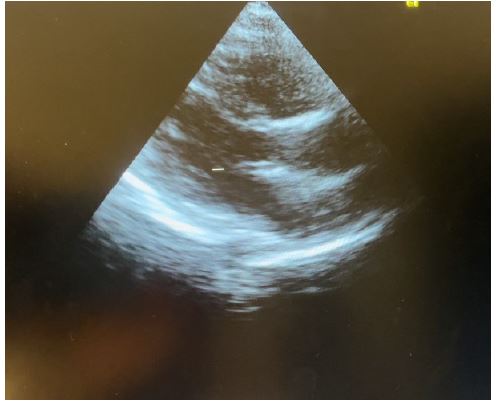

Figure 8: Showing parasternal long axis view of 2 weeks post discharge echo control with no pericardial effusion

Transthoracic echocardiography is the best diagnostic imaging, useful in diagnosis and management of tuberculous pericardial effusion. Echocardiography can provide an estimate of the size of effusions. Generally, the size of the effusion on echocardiography indicates the volume of pericardial fluid as follows: small (<10 mm), which corresponds to 50-100 mL pericardial fluid; moderate (10-20 mm), corresponding to 100 - 500 mL pericardial fluid and large (>20 mm), corresponding to >500 mL pericardial fluid [19] . The study of Diakité et al. showed 18% of moderate abundance and 81% of high abundance among 49 cases of tuberculous pericarditis [6].